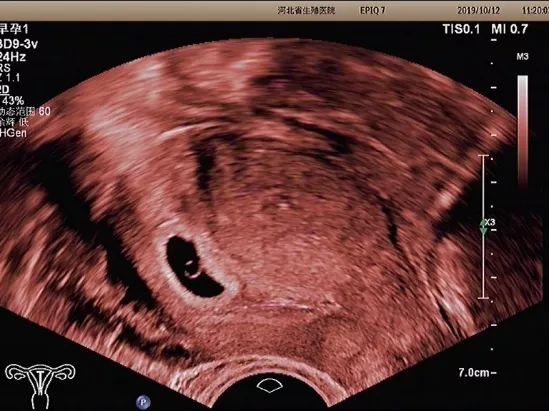

确定妊娠囊是否在宫腔内,妊娠囊在宫腔内的位置、数目及大小。妊娠囊的大小可随孕周增长而增长。

卵黄囊

卵黄囊是妊娠囊内超声能发现的第一个解剖结构。当超声发现卵黄囊,即可以确定妊娠。正常的卵黄囊直径约3~8mm,卵黄囊过大、过小或不显示及变形均提示妊娠结局不良。

胚芽

可根据胚芽长度评估孕周,有无心管搏动,确定胚胎是否存活。